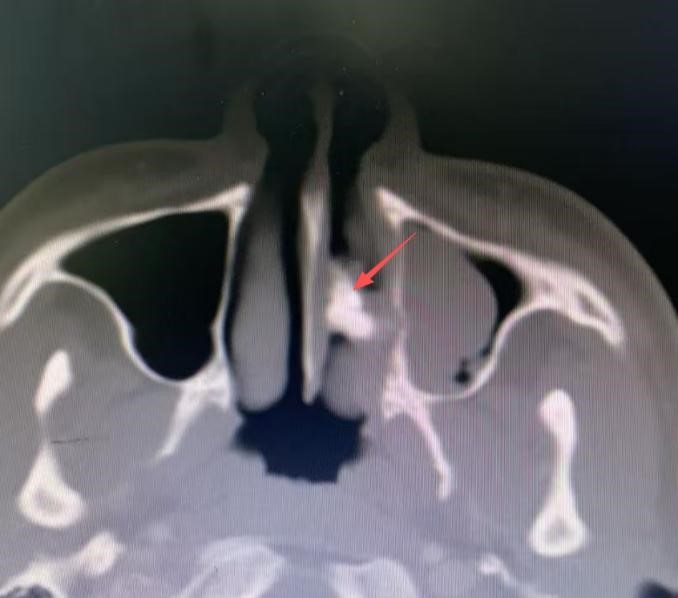

接诊的杨中纯副主任医师为李可进行鼻内镜检查时发现,其左侧鼻腔底部有一处呈粉色肉芽状的隆起,肉芽底部质地偏硬,呈现出沙砾样变化,表面并不光滑。与此同时,医生还检查了李可的口腔,奇怪的是,他口腔内牙齿完好,且并无严重的鼻部外伤史。这个“硬家伙”究竟是什么呢?为进一步揭开谜团,医生为李可进行了鼻腔CT检查。结果令人大吃一惊,这个困扰他多年的“鼻内硬物”——竟是一颗鼻腔异位牙!

箭头所指的就是鼻腔异位牙

“鼻腔异位牙俗称‘额外牙’或‘多生牙’,是一种牙齿发育异常现象,多因牙胚受外力作用或先天因素偏离正常位置。”杨中纯表示,这类病例在临床上虽不常见,但常因症状不典型而被误诊。李可的这颗异位牙在鼻腔内长期存在,持续刺激鼻腔黏膜,导致肉芽增生,引发了一系列症状。